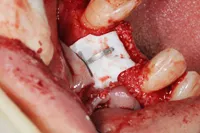

- 骨幅が狭い状態です。

- インプラントを埋めると同時に、骨を作る処置をさせて頂きました。

| 主訴 | 上顎の抜歯した箇所の機能障害・審美障害 |

|---|---|

| 治療方法 | 上顎の欠損部位に1本のインプラントを埋入し、同時に外科的治療で骨造成を行った |

| 治療期間 | 約1年 |

| 通院回数等 | 10回 |

| 費用 | 550,000円(税込) |

| リスク・副作用 | 外科的に骨を作る為、治療後に腫れることがある |